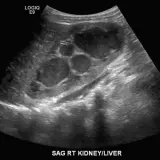

Casos totalmente interactivos con las herramientas que esperaría de un PACS: scroll, ventana, zoom, pan, mediciones, ROI y modo de pantalla completa.

• Anotaciones enlazadas

Anotaciones extensas resaltan los hallazgos clave directamente sobre los casos. Haga clic en los hallazgos enlazados dentro de la descripción del caso para saltar a su ubicación exacta en el estudio.